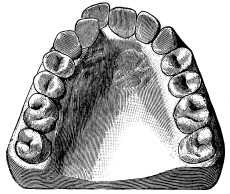

a  b

Fig. 33.

(a) Lower molar with divergent roots. (b) The dotted lines show the direction in which the root can be removed if the tooth is divided as suggested in the text.